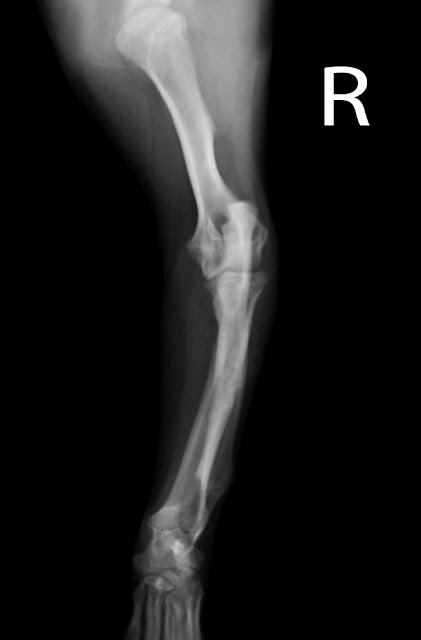

En este caso el paciente es un

cachorro de Labrador de poco más de tres meses y 11 kg que se cayó por las

escaleras de la casa y presenta una cojera de codo de su extremidad anterior

izquierda. Comenzamos la exploración radiográfica con una vista medio lateral

de la extremidad afectada y obtenemos la radiografía siguiente:

A pesar de todas las líneas de

crecimiento se puede apreciar una incongruencia en la articulación del codo, y

la otra vista nos permitirá precisar mejor el problema:

Aunque el posicionamiento del

codo esté ligeramente rotado, podemos concluir que el paciente presenta una

fractura del proceso lateral del cóndilo humeral, y como comentamos

anteriormente la solución a esta fractura debe ser mediante fijación interna

con agujas y tornillos.